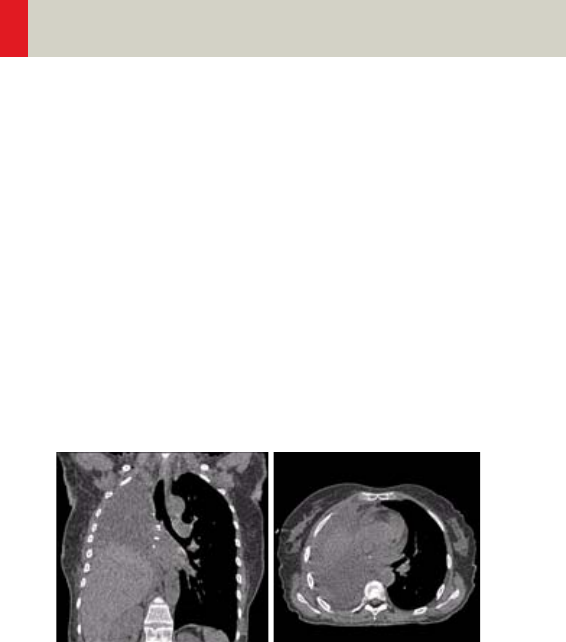

Vascular 360

•Overview 360

- General Hints 363

- Head Kernels 364

- Body Kernels 365